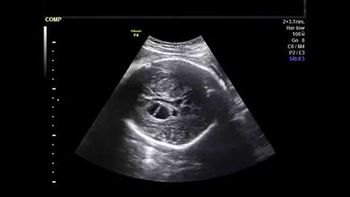

Challenge your diagnostic skills: Anything notable in these images of a fetal heart?